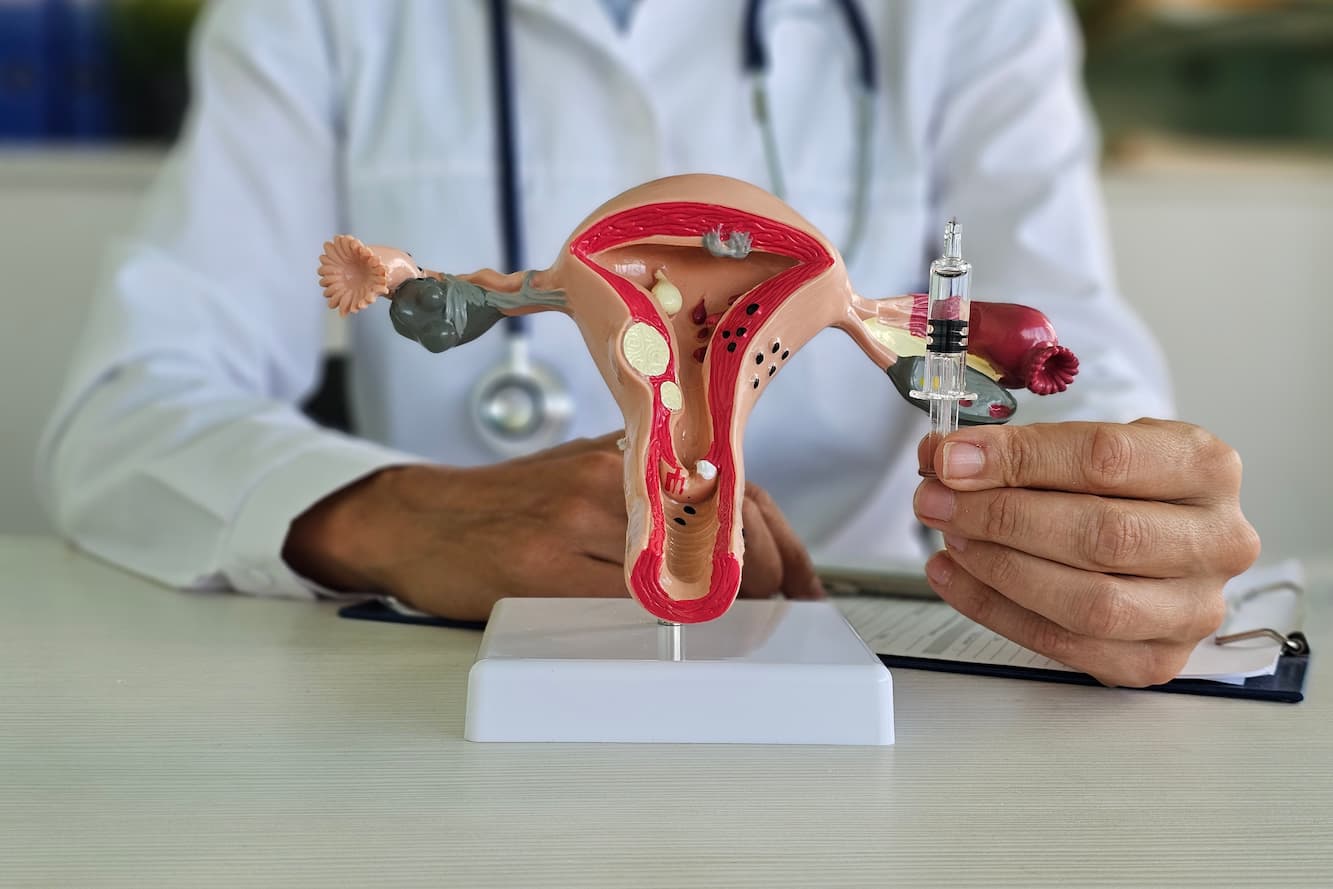

In Vitro Fertilization (IVF) is the most widely used form of assisted reproductive technology. This procedure involves extracting eggs from a woman’s ovaries and combining them with sperm in a laboratory setting, often resulting in fertilization.

In Vitro Fertilization (IVF) is the most widely used form of assisted reproductive technology. This procedure involves extracting eggs from a woman’s ovaries and combining them with sperm in a laboratory setting, often resulting in fertilization.